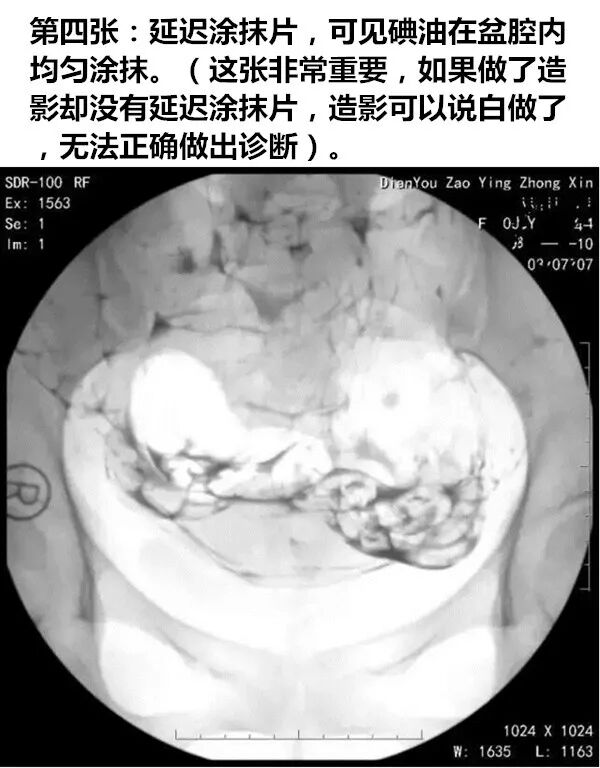

造影的时候,几乎所有的人都会马上追着问,“大夫,我通不通?”。大夫都会告诉你,要等延迟涂抹片出来才可以确定。那什么是“延迟涂抹片”呢?这个东西真的非常非常重要,一切不做延迟涂抹片的造影都是白做。

延迟涂抹片就是在造影操作后(如造影剂用的是碘油,则为术后12-24小时,如造影剂用的是碘水,则为术后10-40分钟内),在盆腔再照一张X光片,观察盆腔内碘油弥散情况。

如下图所示,这是一张正常的延迟涂抹片,碘油在盆腔内均匀弥散。

延迟涂抹片对于最后确诊输卵管的状态非常重要,如果没有,会影响输卵管诊断的准确性!